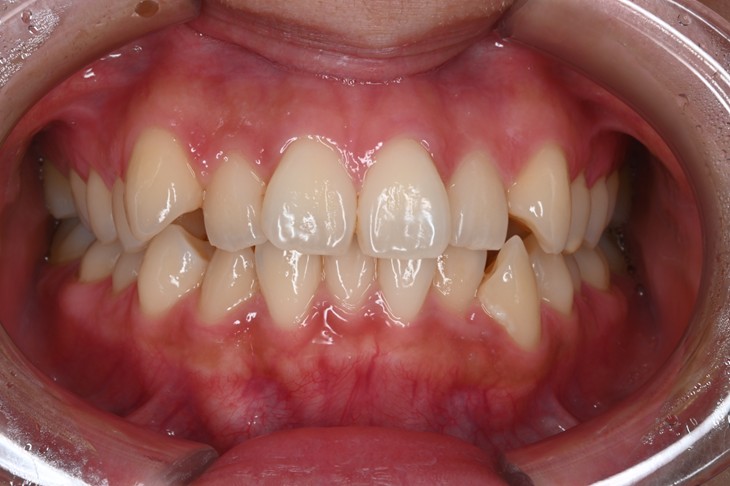

症例1:前歯のガタつきが気になる

| 患者様データ | 20代 女性 |

| 来院主訴 | 口元を下げたい。前歯のガタつきが気になる。 |

| 治療内容 | 口元を下げるために上下4本抜歯し、インビザラインにてマウスピース矯正を開始しました。かみ合わせを整えるためにゴムかけを行いました。 |

| 概算治療費 | 約90万円 |

| 治療期間 | 1年10ヶ月 |

| 通院回数 | 10回 |